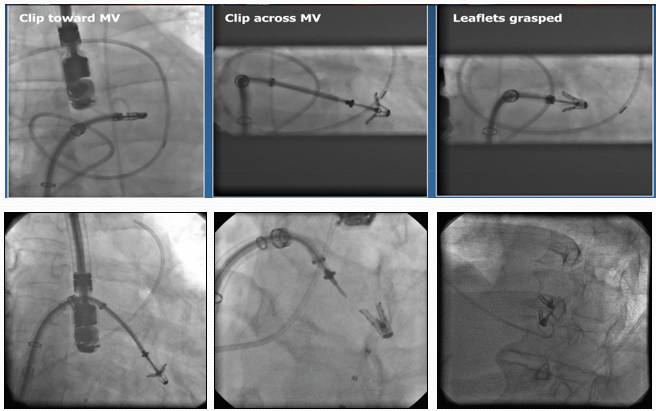

技术原理:使用特制的二尖瓣夹合器,经股静脉进入,穿刺房间隔,进入左心房及左室,在三维超声及DSA引导下,使用二尖瓣夹合器夹住二尖瓣前、后叶的中部,使二尖瓣在收缩期由大的单孔变成小的双孔,从而减少二尖瓣反流

手术流程

Percutaneous Mitral Valve Repair

MitraClip? System

[7]

MitraClip技术过程